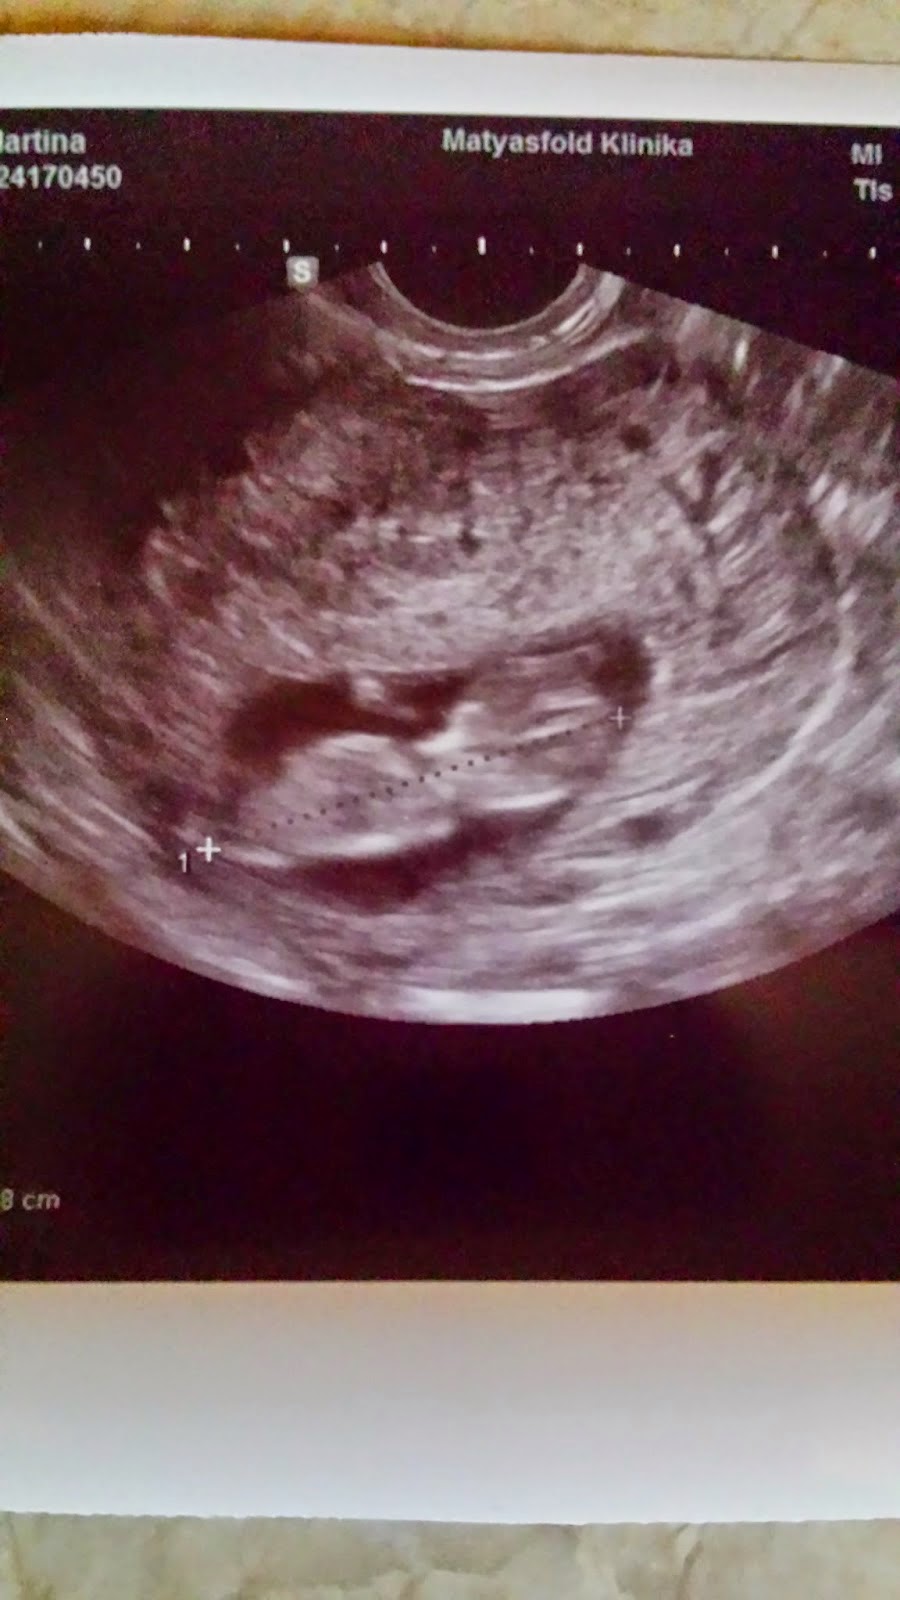

Ma is hoztam uhu képet. Ez volt az utolsó vizsgálat a genetikai előtt. ( az jövő csütörtök)

Bé 10 hetes 4 naposan 4,28 cm volt tegnap A képen asszem háttal van.

A dokibácsi sokat nézegette, azt mondta, hogy korának megfelelő - pont így kell kinéznie - és nyugodjak meg, mert "rendben van a kisbaba" .